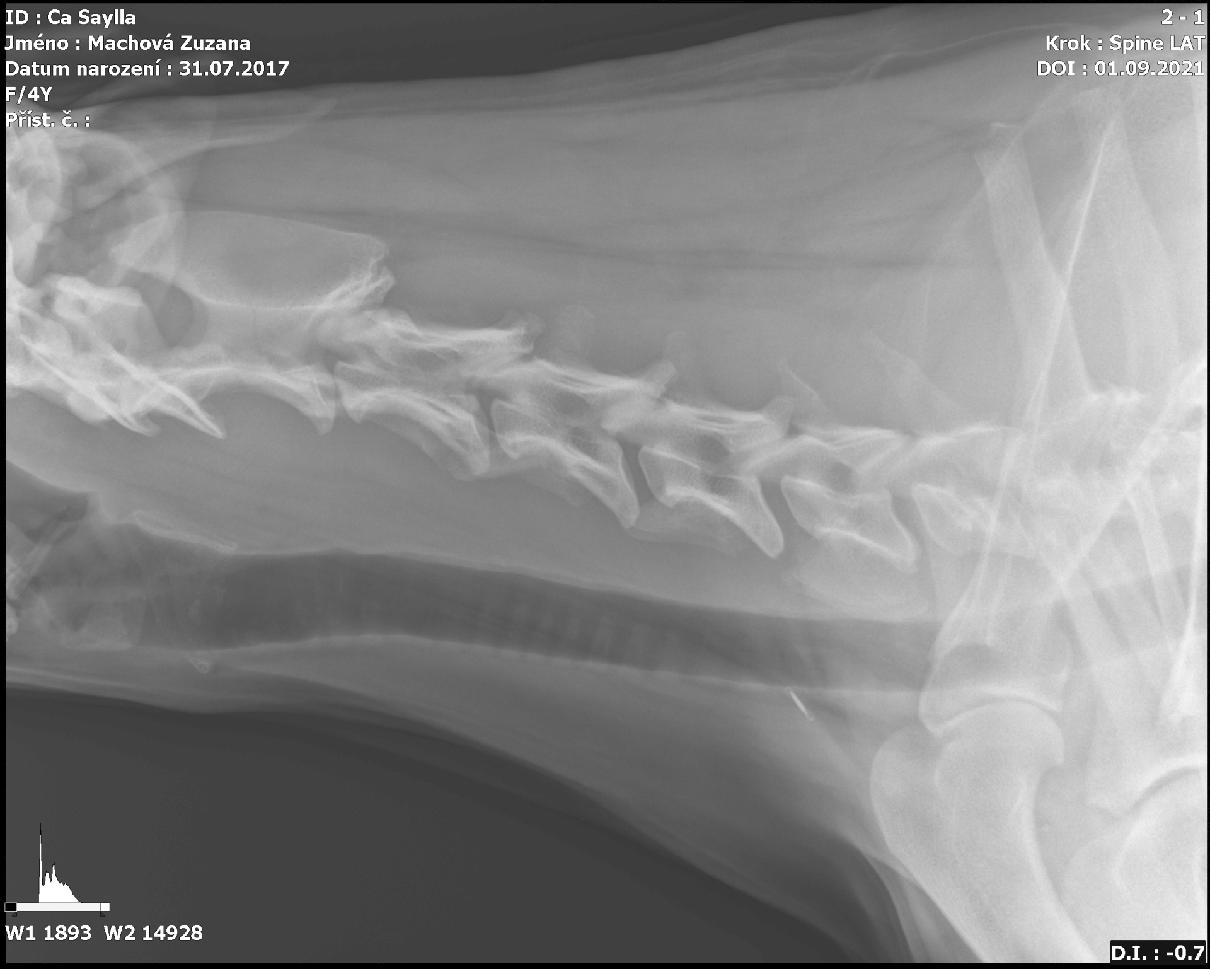

Dobrý den, mám dobrmanku 4 roky stará, kulhá skoro 14 dní na přední nohu. Momentálně je po rtg snímcích. Bylo nám řečeno, že má abnormalitu na sedmém obratli krční páteře a kulhání souvisí s tím. Bolest vystřeluje do pravé přední končetiny, sem tam škobrtne zadníma už dlouhodobě, těžko se jí vstává, občas se počůrává samovolně, je pohybově pomalejší už delší dobu. Na nohu nechce vůbec šlápnout, natož chodit. Po klidovém režimu jako by jí nic nebylo, než vyrazíme na procházku. Do večera opět nechodí. Moc prosím, poznáte dle snímku Wobblera??? Byla nám doporučena rehabilitace, ale pokud má Wobblera, pak jí bude k ničemu. Moc děkuji za odpověď, Machová

Dobrý den. Bohužel tento rtg snímek není relevantní k vyjádření zda-li se jedná o Wobleruv syndrom. Doporučuji navštívit specialistu-ortopeda.S pozdravem MVDr Jančík.